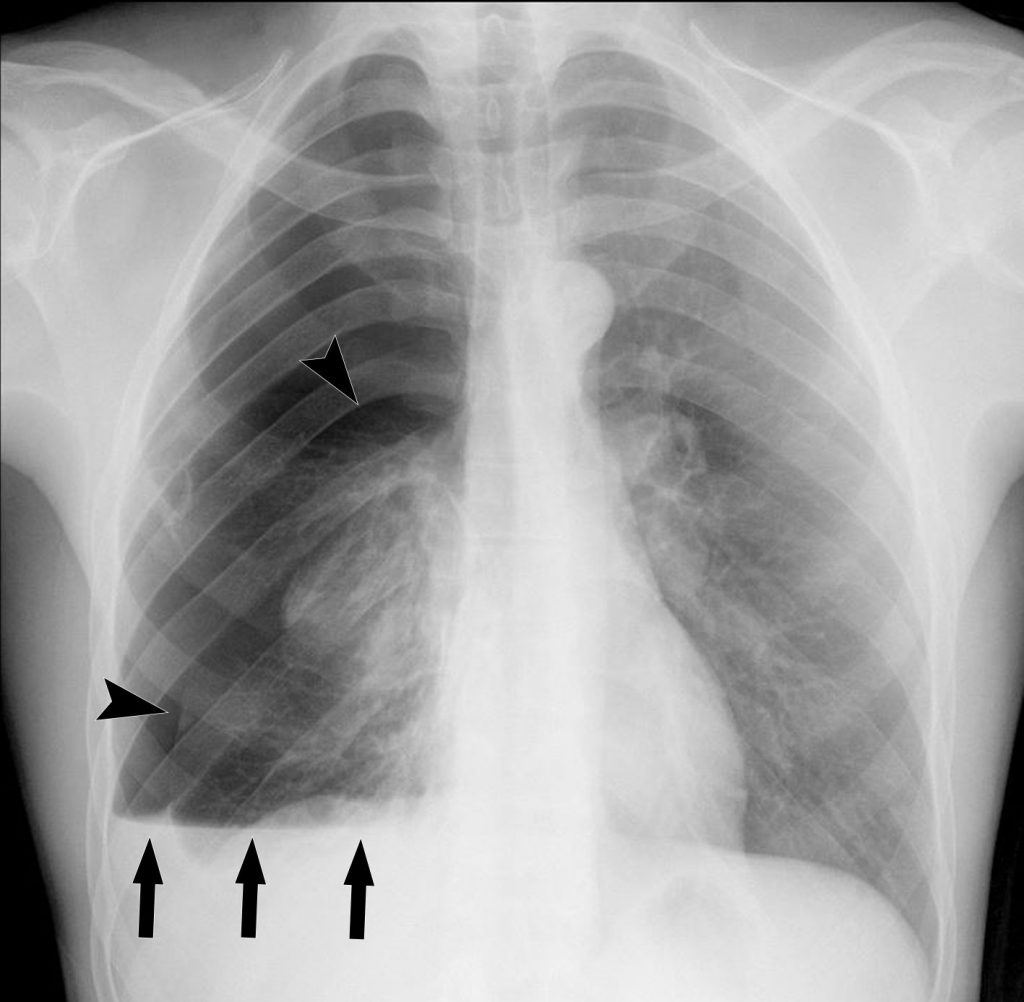

Un épanchement volumineux peut être à l’origine d’une opacité complète d’un hémithorax. Devant un épanchement abondant, il faut toujours évaluer si l’épanchement est compressif en recherchant un refoulement du médiastin vers le côté opposé, ce qui est un signe de gravité (figure 91.5).

Fig. 91.5. Radiographie de face et scanner d’un épanchement pleural droit compressif.

L’hémithorax droit est entièrement opaque (astérisque en A) et la trachée est légèrement refoulée vers la gauche (flèches en A). Le scanner chez le même patient montre l’épanchement pleural droit de grande abondance (astérisque en B) refoulant le médiastin vers la gauche (flèches en B).

Source : CERF, CNEBMN, 2022.

Enfin, lorsqu’un épanchement est cloisonné, la limite interne de l’opacité peut être convexe et sa topographie non gravito-dépendante (figure 91.6).

Fig. 91.6. Radiographie de face debout et scanner d’un épanchement pleural droit cloisonné.

L’épanchement pleural droit présente une limite interne convexe sur la radiographie (flèches en A) et le scanner (flèches en B) ce qui indique qu’il est cloisonné.